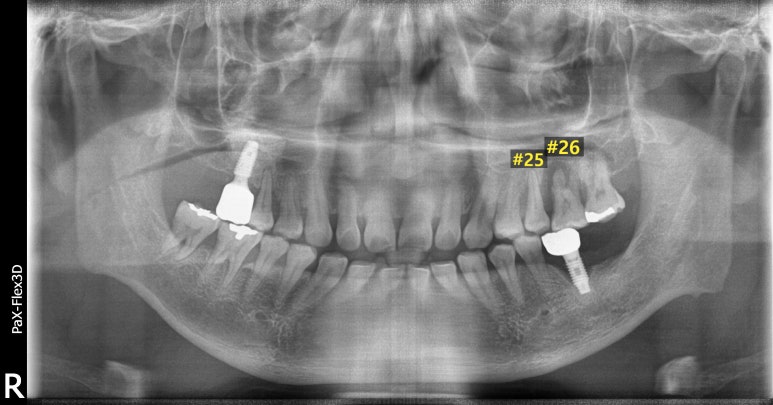

환자분의 첫 내원 시 사진입니다.

거주하고 계시는 동네 치과에서 #25, 26 치아 발치 후 임플란트 치료가 필요하다는 말을 들었는데

저희 디데이치과가 위치한 선릉역 근처에서 근무하고 계셔서 내원해주셨다고 합니다.

우선 살펴보면 임플란트가 필요한 치아는 왼쪽 위 어금니 2개였는데요.

#25 치아는 임플란트를 식립하기에 잇몸뼈의 양이 부족하고 뼈의 상태도 좋지 않아

뼈이식을 진행한 후 잇몸뼈가 단단하게 자리잡힐 때까지 기다렸다가 임플란트를 식립하는

지연식립이 필요한 것으로 진단했습니다.

옆에 있는 #26 치아는 염증이 심해 잇몸뼈가 상당히 녹아 치아 뿌리 일부가 노출되어 있는 상태였습니다.

하루 빨리 발치 후 임플란트를 식립해야 하는 상태였는데,

상악동이라고 하는 공기주머니가 많이 내려와 있어 이를 올려주는 상악동거상술까지 진행해야 하는 것으로 진단했습니다.